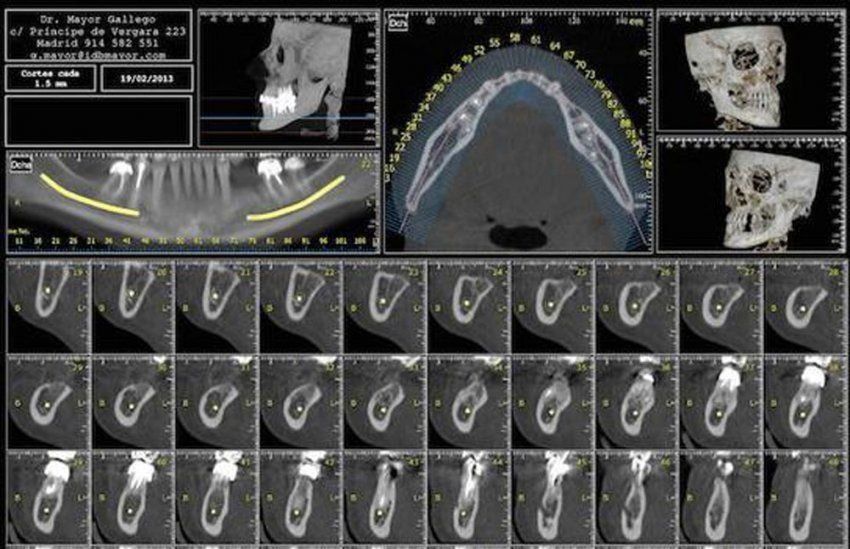

En palabras del propio Dr. Jorge Costa: "el escáner dental, o la conocida técnica de Dentascan 3D, nos permite ver con gran nitidez y detalles la estructura ósea y muscular de los paciente, gracias a la unión de diferentes imágenes tridimensionales. Aparte de ser un proceso completamente indoloro para el paciente se convierte en una potente herramienta de pronóstico para los profesionales de la salud bucodental".

La prueba diagnóstica Dentascan 3D (también conocida como CBCT) es una técnica muy eficiente para el correcto diagnóstico de los pacientes, sobre todo en aquellos que necesitan un tratamiento de ortodoncia, una cirugía dental o la colocación de uno o varios implantes dentales.

La precisión de las imágenes que se obtienen (tomadas desde diferentes ángulos) permite ver, al detalle, cualquier estructura (ósea o de tejidos blandos) gracias al procedimiento computarizado que une todas las imágenes en una.